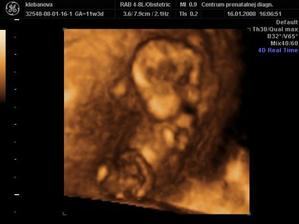

a vonavy kvietocek - anjelicek, mala princeznicka Kristianka Sarah a treti kvietocek je uz v brusku